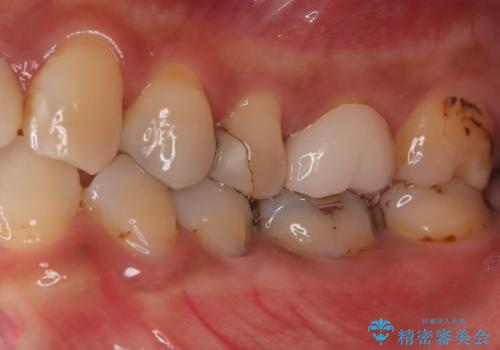

- 「何もしなくても歯が痛む、咬むと歯が痛む」を主訴に来院された患者さんです。検査の結果、歯髄の部分壊死と診断しました。根管治療を行いファイバーコアとオールセラミッククラウンで治療を行いました。

術前に神経の部分壊死と診断しましたが、神経をあけたときに出血が一切無かったので神経が死んでいるという診断は正しかったという事になります。

神経が死んでしまった原因はプラスチック(保険適用治療)の被せ物が劣化し歯と被せ物の間に生じた隙間からのリークが原因だと考えます。